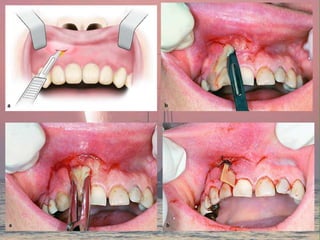

Methods of drainage

• Through the root canal

• Through the socket by extraction

• Through fenestraion of the alveolar bone

• Through incision

Indications for incision and drainage

• Signs of pus accumulation

• When the involved compartment are

inaccessible

• Serious and rapidly evolving infections of

neck and floor of the mouth

Principle of incision and drainage

1. Should put on healthy skin and mucosa as possible , in area

of maximum fluctuancy

2. Esthetically accepted area

3. should include only skin and subcutaneous tissues and

dissection through deeper tissue should be done bluntly

4.Drain should be used after after evacuation of the pus

5. Wound margins should be cleaned daily to remove clots and

debris

6. Sample of pus should be obtained and sent to the laboratory

for culture and sensetivity test

Prior to surgical drainage,

a sterile aspirate is obtained for culture and sensitivity

Palatal abscess , incision parallel to the greater palatine vessels

An incision at submandibular region should be placed two fingers’ breadth

below the lower border to avoid injury of the marginal mandibular branch of the facial

nerve